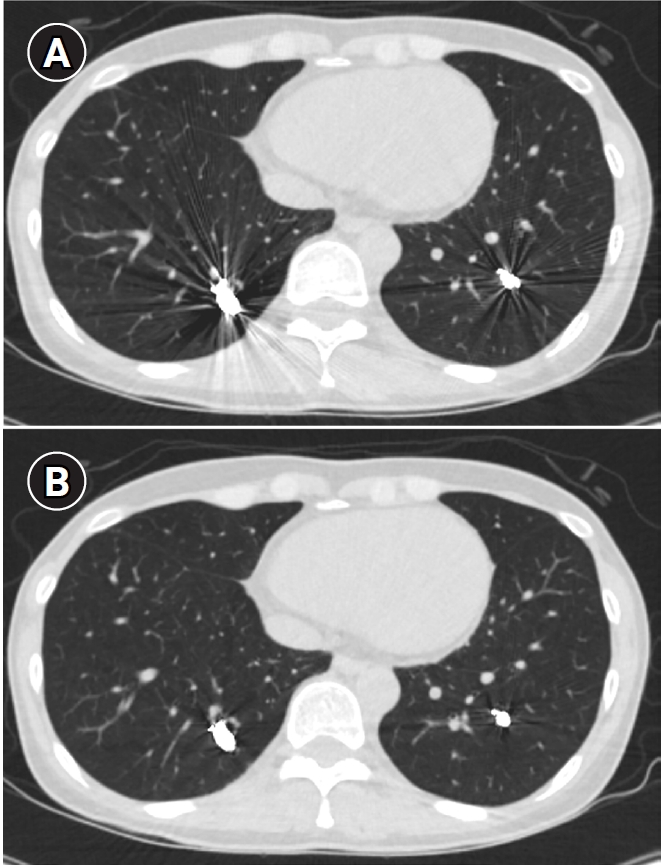

Fig. 8. Computed tomographic (CT) images of a pulmonary arteriovenous malformation before the procedure (A), 20 days after embolization (B), and at the 6-month follow-up (C). After the procedure, at both 20 days and 6 months, the diameter of the feeding artery and the draining vein is gradually reduced. In this case, the embolization was performed using an Amplatzer vascular plug type IV. Notably, the Amplatzer vascular plug produces minimal beam-hardening artifacts on CT, aiding in the evaluation of vessel diameter and the surrounding parenchyma.

Long-term follow-up after treating PAVMs is needed to detect newly developed PAVMs and to identify persistence or recurrent flow [10,11]. Treatment failure in PAVMs can be classified as recanalization and reperfusion. Recanalization refers to the reopening of blood flow through spaces between the previously placed embolic material (Fig. 6). Reperfusion, on the other hand, occurs when blood flow from an adjacent pulmonary artery reopens the previously embolized distal vein or venous sac (Fig. 7) [32]. As the primary follow-up modality, CT is recommended, but there are currently no specific guidelines on whether or not to use contrast enhancement [33]. It is recommended to perform an initial evaluation by CT about 6 months after PAVM embolization, and then follow-up with CT every 3–5 years thereafter (Fig. 8). In CT follow-up, the evaluation is based on the reduction rate of the venous sac or the draining vein, and the traditional criterion is that there should be at least a 70% reduction in the size of the venous sac or draining vein [34,35]. In recent studies, there have been opinions that this 70% size reduction criterion is too strict. In response, some research using angiographic-confirmed cases or time-resolved magnetic resonance angiography (TR-MRA) has proposed a 50%–60% guideline [36,37]. When using CT, repeated radiation exposure and metal artifacts from the coils can be problematic. By using metal artifact reduction techniques, it is possible to obtain clear images of the surrounding parenchyma, and this also helps in assessing parameters like the draining vein diameter reduction rate (Fig. 9) [38]. Furthermore, low-dose CT protocols may help reduce cumulative radiation exposure during repeated follow-up imaging.